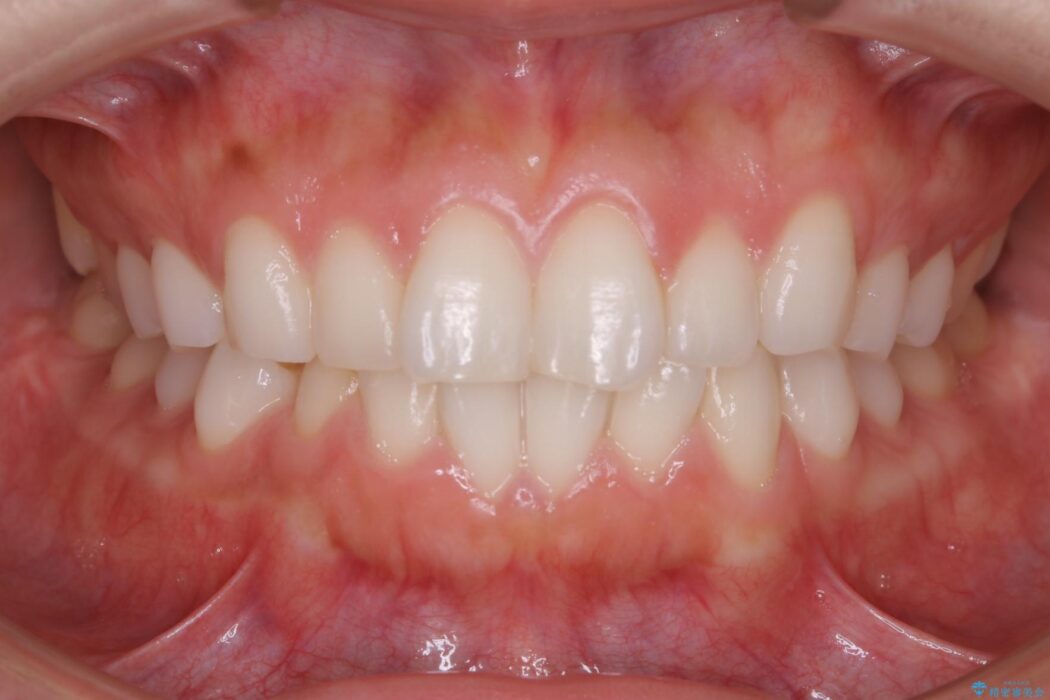

噛み合わせの違和感と前歯のガタガタを主訴に来院されました。

歯軸傾斜と軽度の叢生が見られましたので、通常の位置へと傾きを戻し少量の遠心移動に加えアーチ(歯列弓)の拡大とIPRを施すことで改善していく非抜歯での治療計画としました。

咬合調整は咬合力を複数の歯に均等に分散することで歯の負担を少なくでき、歯の長持ちに繋がります。

噛み合わせが改善されたことによりしっかり噛めるようになったと喜んでいただきました。